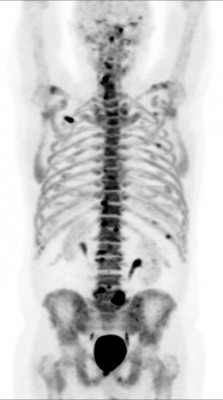

(рус) Позитронная эмиссионная томография (ПЭТ/КТ) всего тела с 18F-фторидом натрия